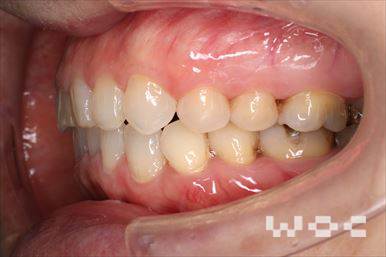

八重歯・叢生上のみ舌側矯正、下はエッジワイズ装置

上は舌側矯正を希望。ガタガタ(叢生)が強い。上顎右側中切歯・側切歯が歯科治療で連結してあったがそれを除去してから治療開始しました。

- 年齢:23歳女性

- 主訴:上下前歯のガタガタが気になる

- 基本矯正料金:103万円

- 治療期間:2年2ヶ月

- 非抜歯